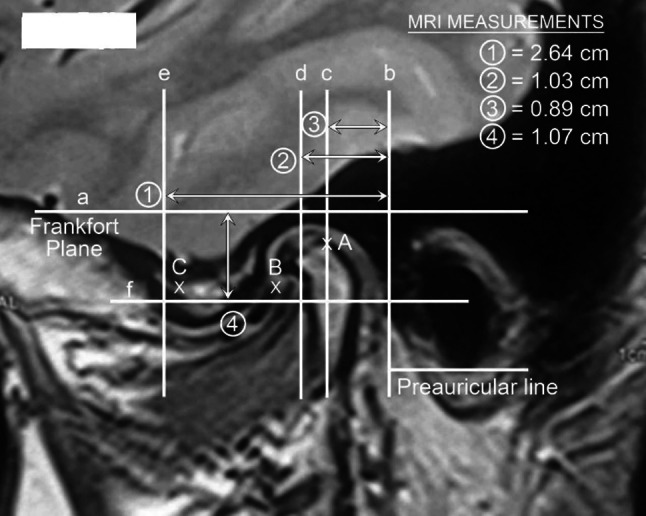

Besides examining the MRI and CT scans for diagnosis of the intra-articular pathology, the MRI is carefully examined and measured to determine the precise size of the patients TMJ. These measures are lateral to define the anatomy of the joint and distances both vertically and horizontally to determine the points of insertion of cannulae and instruments (Figs. 1, 2).

Sagittal MRI showing marking and measurements

Sagittal Scan

Line (a) is the Frankfort plane which is a horizontal line from the superior margin of the external auditory meatus to the infraorbital rim.

Line (b) is the vertical line immediately anterior to the tragus and in perpendicular to the Frankfort line (preauricular line).

Line (c) is parallel to the preauricular line and passes through the highest point of the glenoid fossa.

Line (d) is parallel to the preauricular line and passes through the posterior limit of the temporal eminence.

Line (e) is parallel to the preauricular line at the anterior limit of the temporal eminence.

Line (f) is a line parallel to the Frankfort plane at the vertical height of the articular eminence.

The following measurements are then recorded.

1. Distance from the preauricular line to the anterior eminence line.

2. Distance from the preauricular line to the posterior eminence line.

3. Distance from the preauricular line to the highest point of the glenoid fossa.

4. Distance from the Frankfort horizontal line to the height of the articular eminence.

These measurements are recorded in mm and are computer-derived measurement taken directly off the sagittal MRI scans and available for ready intra-operative reference by the surgeon.

The following points of insertion are defined (Fig. 1).

Point A

Along line (c) and into the maximum depth of the glenoid fossa.

Point B

At the angle of line (b) and (f).

Point C

At the angle of line (d) and (f).